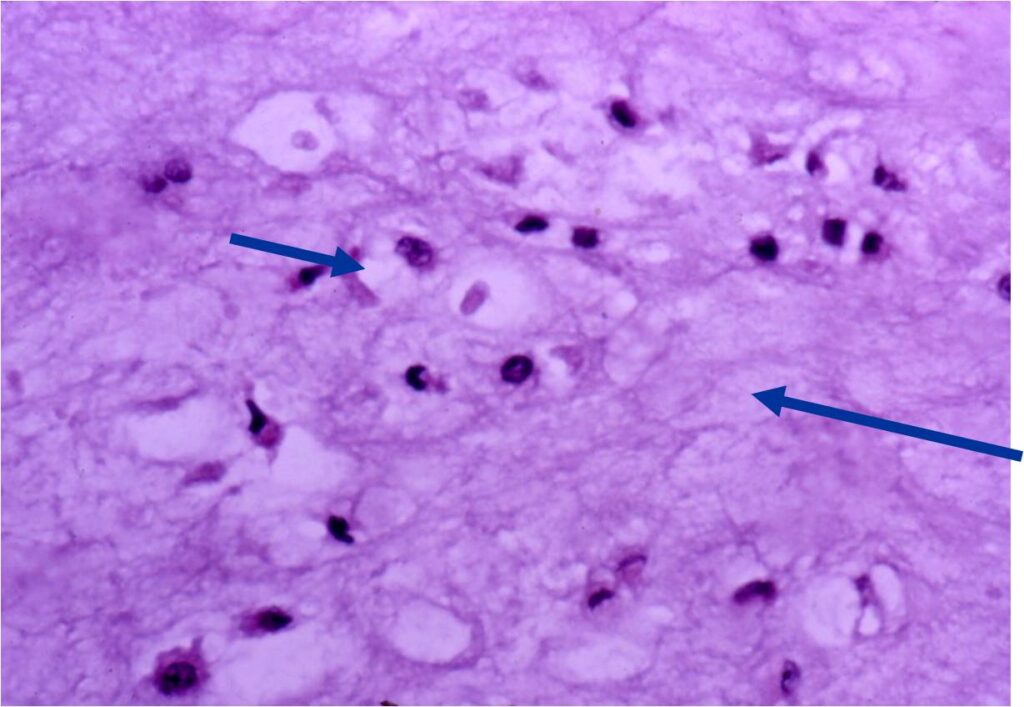

- Cells are in lacunae and have small dark nuclei

- Low cell count, cells appear bland with few chondrocytes and are similar size and shape

- Although some enchondromas may have areas that are hypercellular and may have two or three cells within a lacunae

- Enchondromas of digits can have hypercellularity, bi and trinucleated cells and myxoid change and still be considered benign

- Hypercellular with large number of binucleated chondrocytes

- Higher degree of cellularity and atypia compared to isolated enchondroma